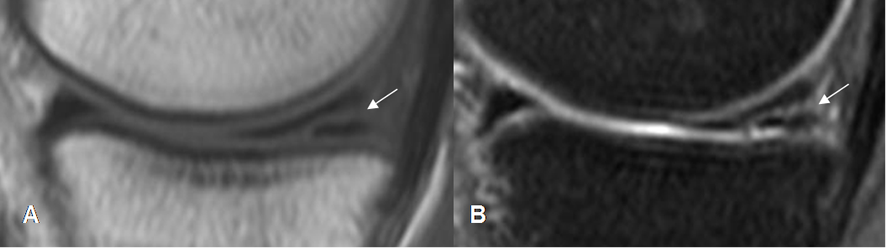

Fig 70. Ruptura meniscal.

A: RM sagital en T1 y B: RM sagital en T2. Imagen en sentido oblicuo, hiperintensa en ambas secuencias, que se comunica con las superficies articulares superior e inferior, por ruptura.